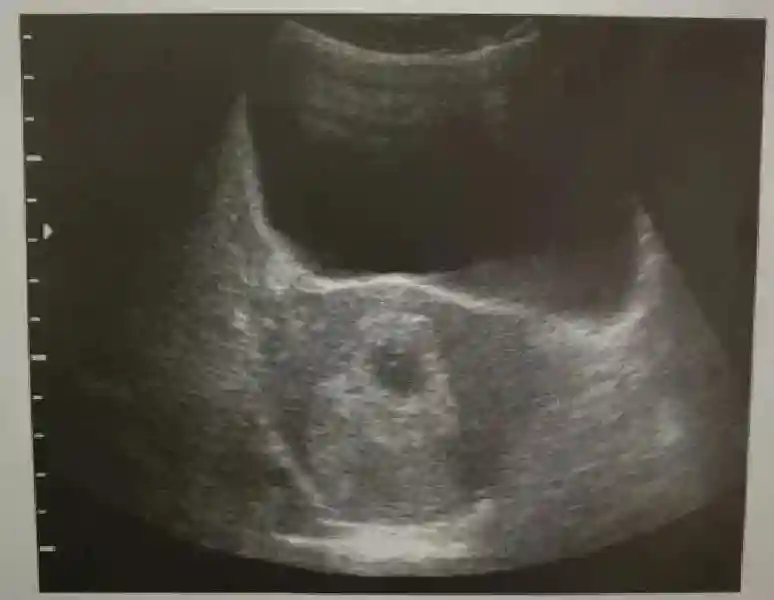

1️⃣妊娠囊:早期妊娠囊:正常妊娠囊位于宫腔上段,表现为宫腔内圆形或椭圆形的无回声区,周边为完整的、厚度均匀的强回声环,强回声环厚度≥2mm,强回声是妊娠绒毛的回声,随着妊娠囊的增大,形成特征性的“双环征” ,10周以后消失。正常的妊娠囊增长速度是平均 1 mm /d。